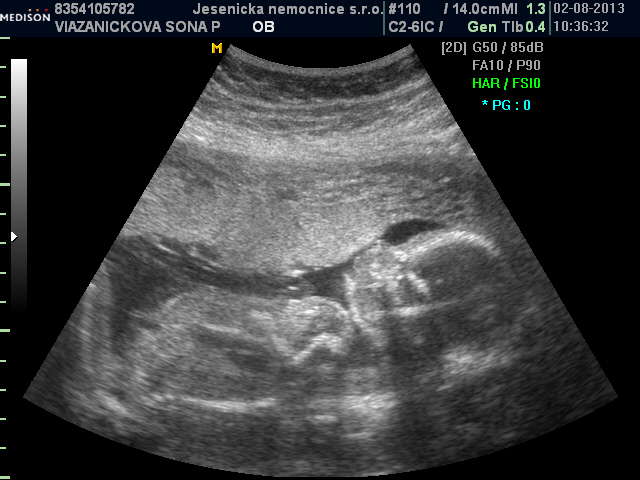

Baruš držím pěsti pro štěstí, ať je vše v pořádku a jste brzo doma. Jinak my jsme byli v pátek na velkém UTZ a na srdíčku, srdíčko naprosto v pořádku, čekáme chlapečka Tomáška, doktorka byla skvělá. Jinak malej pořát kopal, dával si ruku pod bradu, jakoby přemýšlel, kdo to na něj kouká, mlaskal, vyplazoval jazyk, Verunka z toho byla úplně hotová a taťka taky. Jak se mu rozzářily očička.